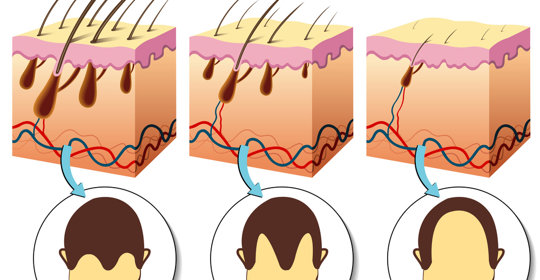

新生兒掉髮:檢查專案與處理措施

新生兒掉髮:原因及預後

新生兒掉髮:原因與護理

新生兒掉髮:輕微顫抖正常,嚴重掉髮需就診

新生兒掉髮:原因與處理

新生兒掉髮:原因和處理方法